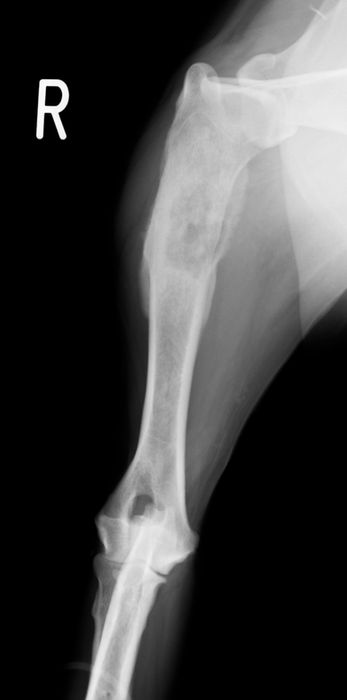

骨折治療について

動物も人間と同じように骨折や脱臼をします。

原因として交通事故などの大きな外力によるものもありますが、日本では小型犬が主体となっているため、ソファや抱っこしている所からの落下といった比較的小さな外力でも生じることが多くなっています。

骨折や脱臼の治療は、ギプスなどの処置のみで済むケースもありますが、ほとんどのケースは完全骨折や脱臼を生じますので、手術が必要となります。

当院における骨折治療は、動物のステータス、骨折の発生部位や分類などを考慮して「髄内ピン」「骨プレート」「創外固定器」を単独もしくは組み合わせて使用することで適当な固定力を得られるように施術しています。

●髄内ピン

0.8mm-5.0mmのステンレス製のピンを骨髄内に刺入して固定を行います。